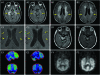

Figures